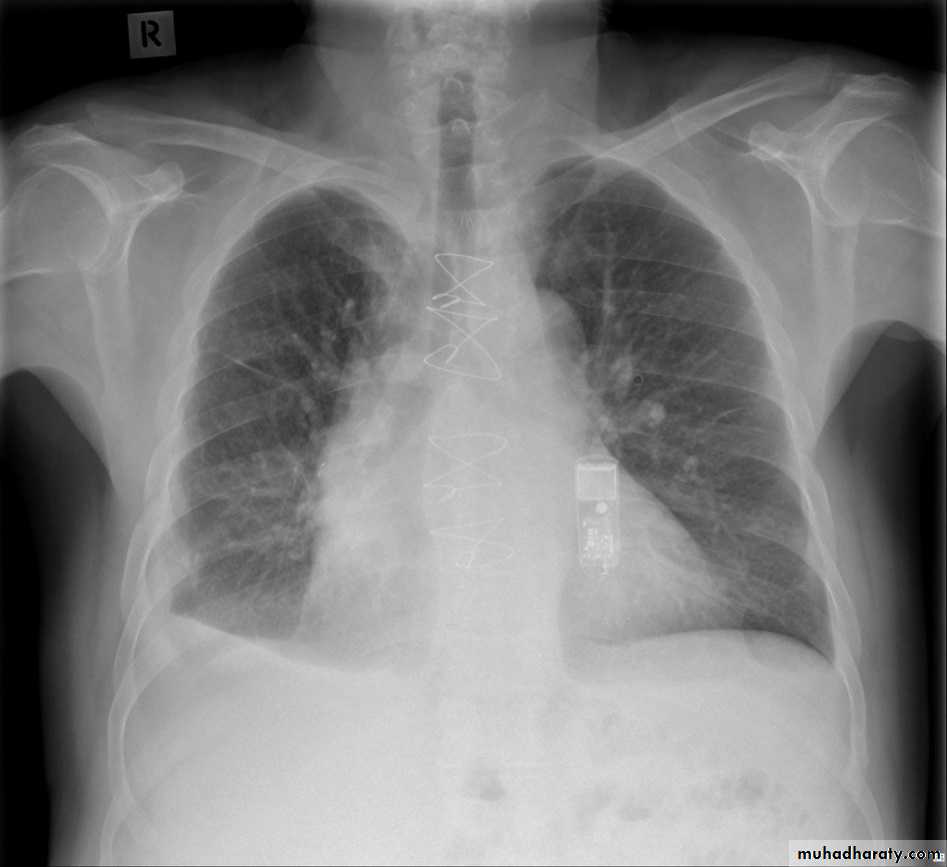

Bronchiactasis

Bronchiectasis refers to abnormal dilatation of the bronchial tree and is seen in a variety of clinical settings. CT is the most accurate modality for diagnosis. It is largely considered irreversibleCauses of bronchiactasias very important to consider

Plain radiograph

Chest x-rays are usually abnormal1. Tram-track opacities are seen in cylindrical bronchiectasis, and

2. air-fluid levels may be seen in cystic bronchiectasis.

Honey comb shadow

3.Overall there appears to be an increase in bronchovascular markings, and bronchi seen end on may appear as ring shadows .

4.Pulmonary vasculature appears ill-defined, thought to represent peri bronchovascular fibrosis .